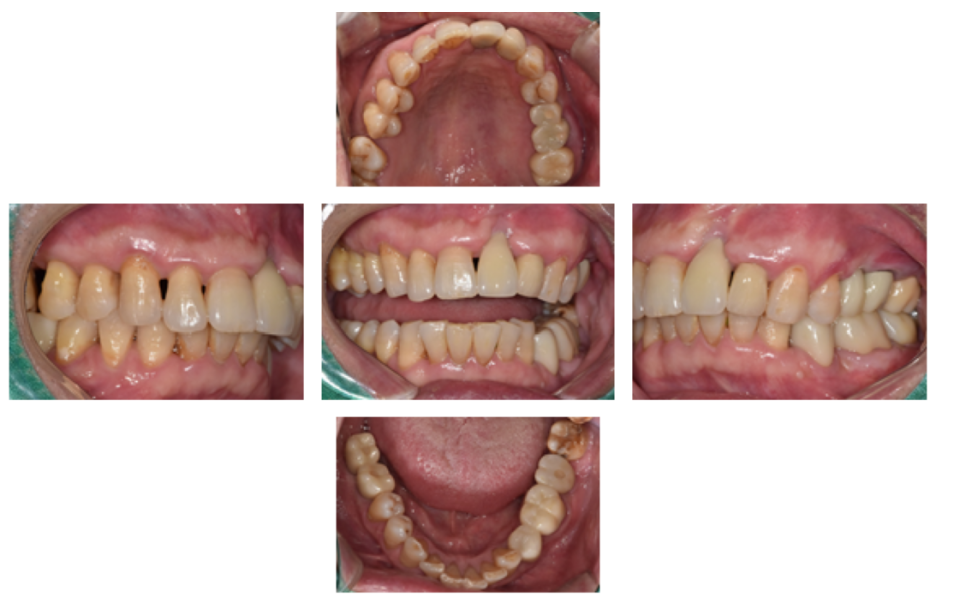

전체적인 구강 판단을 위해

파노라마 엑스레이 사진을 찍었습니다.

왼쪽 큰앞니도 빠져있지만,

오른쪽위 큰어금니, 오른쪽 아래 큰어금니도 발치된 상태였고,

왼쪽 위 브릿지 상태도 좋지는 않았습니다.

왼쪽 아래 큰어금니 하나는 뿌리만 남은 상태였어요.

왼쪽 아래 임플란트 식립 수술 전,

중간확인차 전체 입안 사진 촬영을 하였습니다.

환자분은 오른쪽으로 식사는 잘 하고 계셨고,

왼쪽치료를 진행중인 상태입니다.

왼쪽 앞니의 경우에는,

오랜 염증으로 잇몸과 뼈가 많이 내려간 상태라 보철이 조금 길어지는 한계가 있었습니다...ㅠㅠ